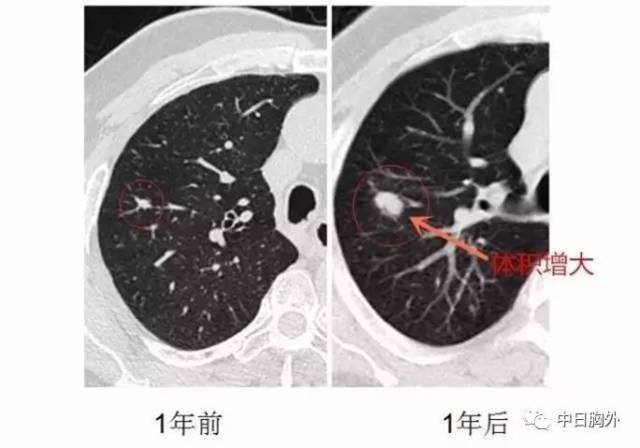

这个案例证实:小于8毫米的肺部小结节,为什么不直接处理?

肺结节读片(21):鉴别11mm的实性结节良恶性的技巧